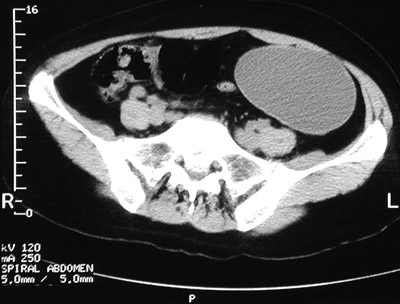

The pelvic CT scan seen here demonstrates an enlarged left ovary with fluid density that has undergone

torsion

, which leads to hemorrhagic infarction. The process produces marked pelvic pain.